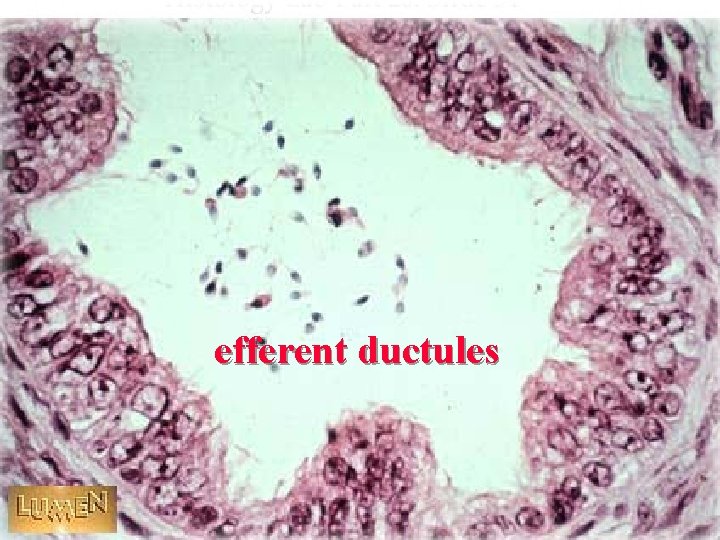

1. efferent ductules l 8 -12,continuous with rete testis l Epi. =high columnar C+low columnar C l Lumen is irregular l cilia is present.

efferent ductules